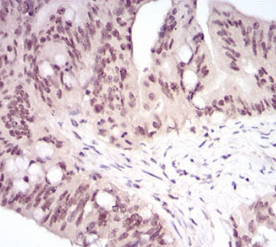

IHC    1/200 - 1/1000